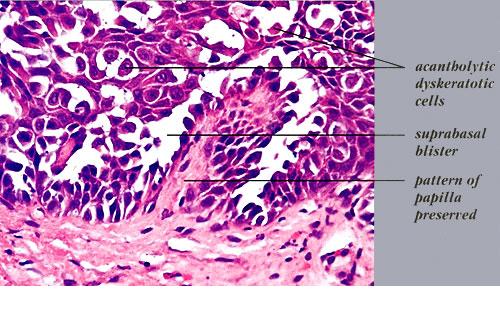

Although, as in Darier's disease, early lesions may show small suprabasal separations, so-called lacunae, fully developed lesions show large separations, that is, vesicles and even bullae, in a predominantly suprabasal position . Villi, which are elongated papillae lined by a single layer of basal cells, protrude upward into the bulla, and in some cases,

narrow strands of epidermal cells proliferate downward into the dermis. Many cells of the detached stratum malpighii show loss of their intercellular bridges; thus, acantholysis affects large portions of the epidermis.

Individual cells and groups of cells usually are seen in large numbers in the bulla cavity. Despite the extensive loss of intercellular bridges, the cells of the detached epidermis in many places show only slight separation from one another, because a few intact intercellular bridges still hold them loosely together. This quite typical feature gives the detached epidermis the appearance of a dilapidated brick wall.

Differentiation of familial benign pemphigus from Darier's disease as a rule is not very difficult, because in Darier's disease, the suprabasal separations usually are smaller, thus appearing as lacunae rather than as bullae; acantholysis is less pronounced, being limited to the lower epidermis, especially the suprabasal region; and dyskeratosis consisting of the formation of corps ronds and grains is much more evident.

Histologically, familial benign pemphigus shares certain features with both Darier's disease and pemphigus vulgaris. In all three diseases, one finds predominantly suprabasal separation of the epidermis caused by acantholysis and resulting in lacunae or bullae and villi formation.